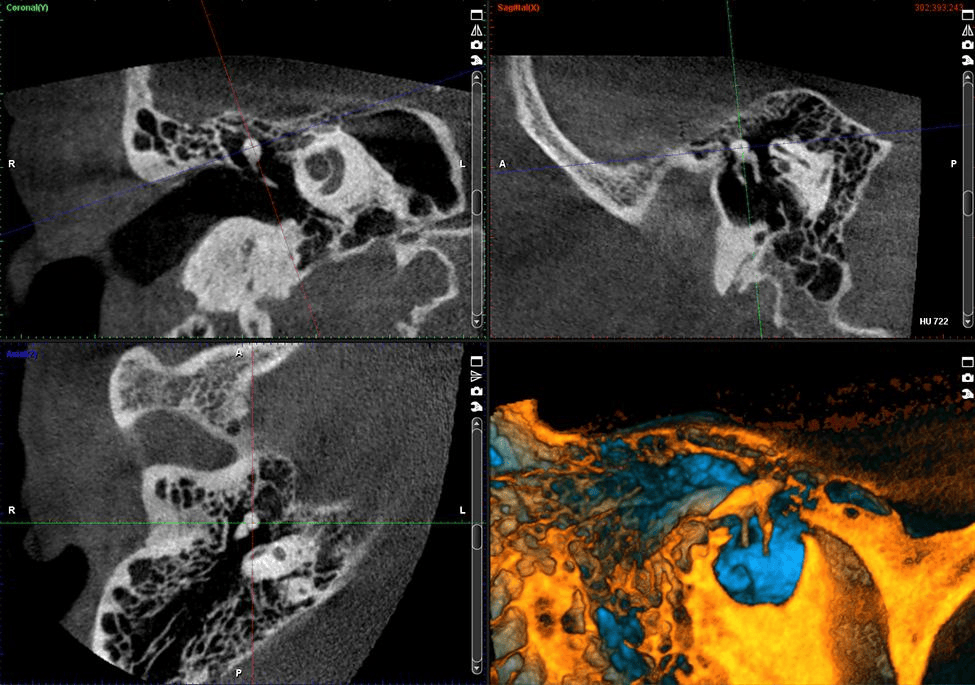

Расширенные возможности ЛОР-визуализации

Размеры вокселей аппарата Planmeca ProMax 3D Plus варьируются от 600 до 75 мкм, а программное обеспечение Planmeca Romexis® предлагает универсальные инструменты для визуализации дыхательных путей, пазух, мягких тканей и мельчайших костных структур в ушах.

ЛОР программы (ухо, горло, нос)

Среднее ухо

• 40x50(34x42) — Изотропный размер вокселя 75 мкм*, 100 мкм, 150 мкм, 200 мкм, 400 мкм

• 80x80(68x68) — изотропный размер вокселя 150 мкм, 200 мкм, 400 мкм

Височная кость

• 80x80(68x68) — Изотропный размер вокселя 150 мкм, 200 мкм